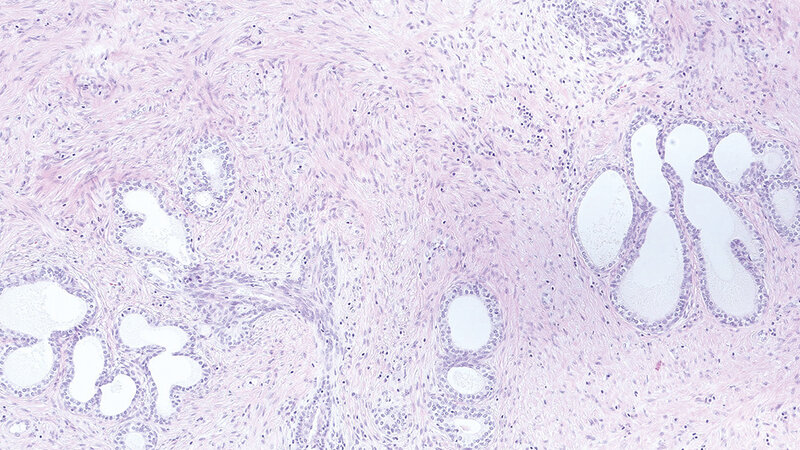

Die Prostata ist ein sehr kleines Organ, das den Männern im Alter allerdings große Probleme bereiten kann. Als Erkrankung ist eine gutartige Prostatavergrößerung im Alter sehr weit verbreitet, aber es gibt auch noch einige weitere benigne und maligne Erkrankungen, die in der Prostata auftreten können. Besonders bei den malignen Erkrankungen kann die Immunhistochemie (IHC) bei der Differenzialdiagnose sehr hilfreich sein.

The prostate is a small organ, but it can cause big problems for older men. A benign prostatic hyperplasia is common in old age. There are several other benign or malignant diseases that can occur in the prostate. Immunohistochemistry can be helpful in the differential diagnosis, particularly of malignant diseases.